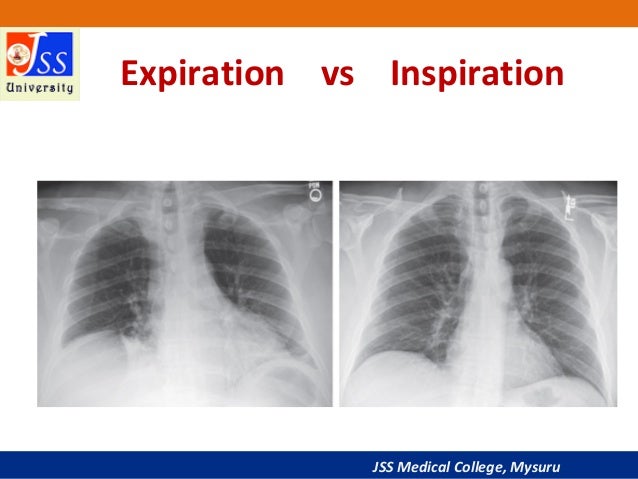

BASICS OF CHEST X RAY PART3 INSPIRATION VS EXPIRATION QUALITY OF X RAY

Approach To Chest X Ray And Interpretation

Normal Difference Between Chest Inspiration And Expiration - 2025 DIY